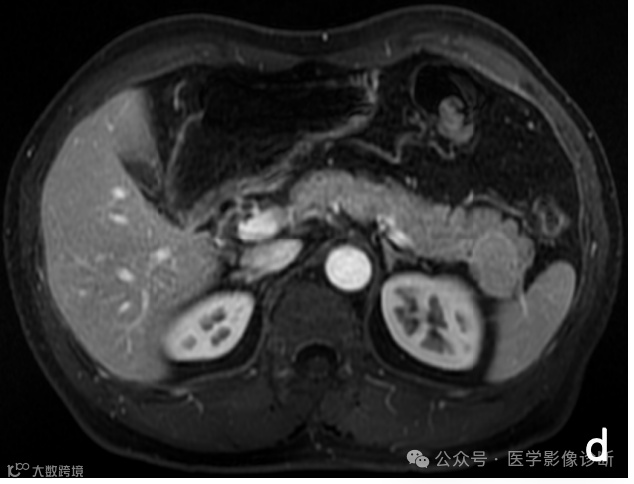

胰腺尾部占位性病变,轴位MRI T1WI (a)、T2WI/FS (b)、T1WI/FS (c)、增强(d)序列均显示病变信号与脾脏相似,但是放射医生诊断为相对常见的胰腺神经内分泌肿瘤,而非罕见的异位脾脏。手术病理证实为胰腺内异位脾脏。